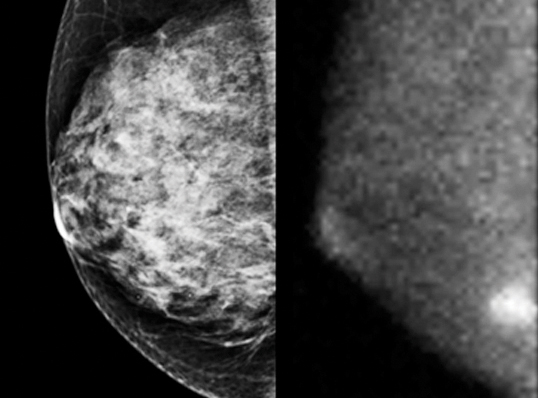

For tumors hidden within dense tissue, traditional screening sometimes isn’t detailed enough to reveal the cancer. This is especially true in the case of breast cancer. For the 30 percent of women with dense breast tissue, traditional X-ray mammography doesn’t work well because, in an X-ray image, dense tissue appears opaque and white, just like a tumor.

Using detectors and integrated circuits designed for particle-physics experiments, a group of researchers in particle physics, nuclear medicine, medical physics and astronomy developed a compact semiconductor-based imager with high spatial resolution that reveals tumors even within dense tissue.

These gamma-ray mammography cameras use cadmium-zinc-telluride detectors and are highly accurate, says Michael K. O’Connor, a professor of radiologic physics at Mayo Clinic in Rochester, Minnesota.

The cameras offer improved resolution of tissue with their 1.6-millimeter pixel size, about two times better than conventional gamma cameras. They can also image all the way to the edge of the detector, unlike traditional gamma cameras, which have a large ring of dead space around the center.

“With these cameras you can detect tumors in the 5- to 10-millimeter range,” O’Connor says. “Ten millimeters is an important number for tumor size: Once you can detect a tumor this size or smaller, the prognosis gets much better. With a tumor of this size, the chances are that it’s localized and surgical removal of the tumor can cure the patient.”

To detect potentially dangerous cell growth using such a gamma camera, a physician injects a radioactive tracer into the patient’s arm. Due to cancer cells’ high metabolic activity, these cells accumulate more of the tracer than normal cells and so emit more gamma rays as it decays. The camera can detect this and records a high-resolution image of the tumor.

There are approximately 15 to 20 of these advanced gamma cameras currently in use at hospitals around the United States, and they are proving very successful. While traditional mammography reveals about three tumors for each 1000 women with dense tissue screened, large clinical trials at Mayo Clinic have shown that the gamma cameras reveal about 10 cancers for each 1000 women with dense tissue screened.

“Because dense tissue diminishes the ability of mammography to detect the cancer, but also increases a woman’s chances of getting breast cancer, it’s important to find alternative techniques,” O’Connor says. “This is one of the most promising. We’ve really been astounded by how well it works.”